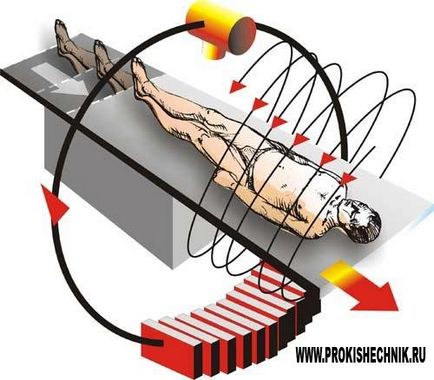

A működési elve az MRI

Abban a vizsgálatban, testrészben MRI beteg jár, mint lüktető egyenáramú mágneses erőtér és rádiófrekvenciás sugárzás. Ezek alkotják a speciális eszköz - szkennert. Néhány másodpercen belül, akkor a készülék küld egy bizonyos részét a RF pulzus okozza a swing és a lép rezonancia hidrogénatomok a szervezet sejtjei. További speciális berendezések összegyűjti a beérkezett jelzéseket, feldolgozza azokat, és kiadja a háromdimenziós képet a kémiai szerkezet a szövet a környéken.